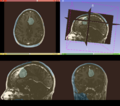

An example implementation of GrowCut has been implemented as a test.

• Topic was generalized to include editor effects based on ITK and VTK

• Porting of CLI tools to run as steered segmenters (Yi, Ivan)